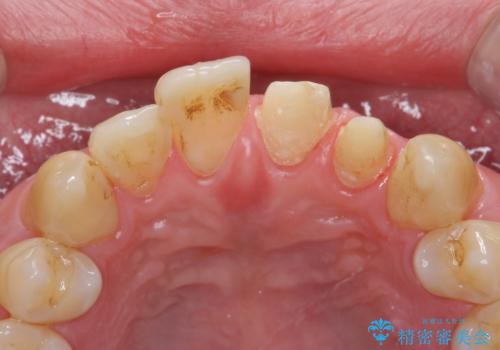

- 前歯の突出を主訴に来院。

全体矯正を行うとなると健康な歯を4本抜歯することになるため、歯は抜かず上だけの部分矯正で最小限で前歯を整えることにしました。

前歯は少し細く削って前に出ないように整えました。

左上の1番目の前歯は神経を取ってある歯でした。今後変色もすすんでいくため、治療のやり直しを行いセラミックでかぶせました。

左上の2番目の前歯は虫歯治療を行い、神経治療まで行っています。